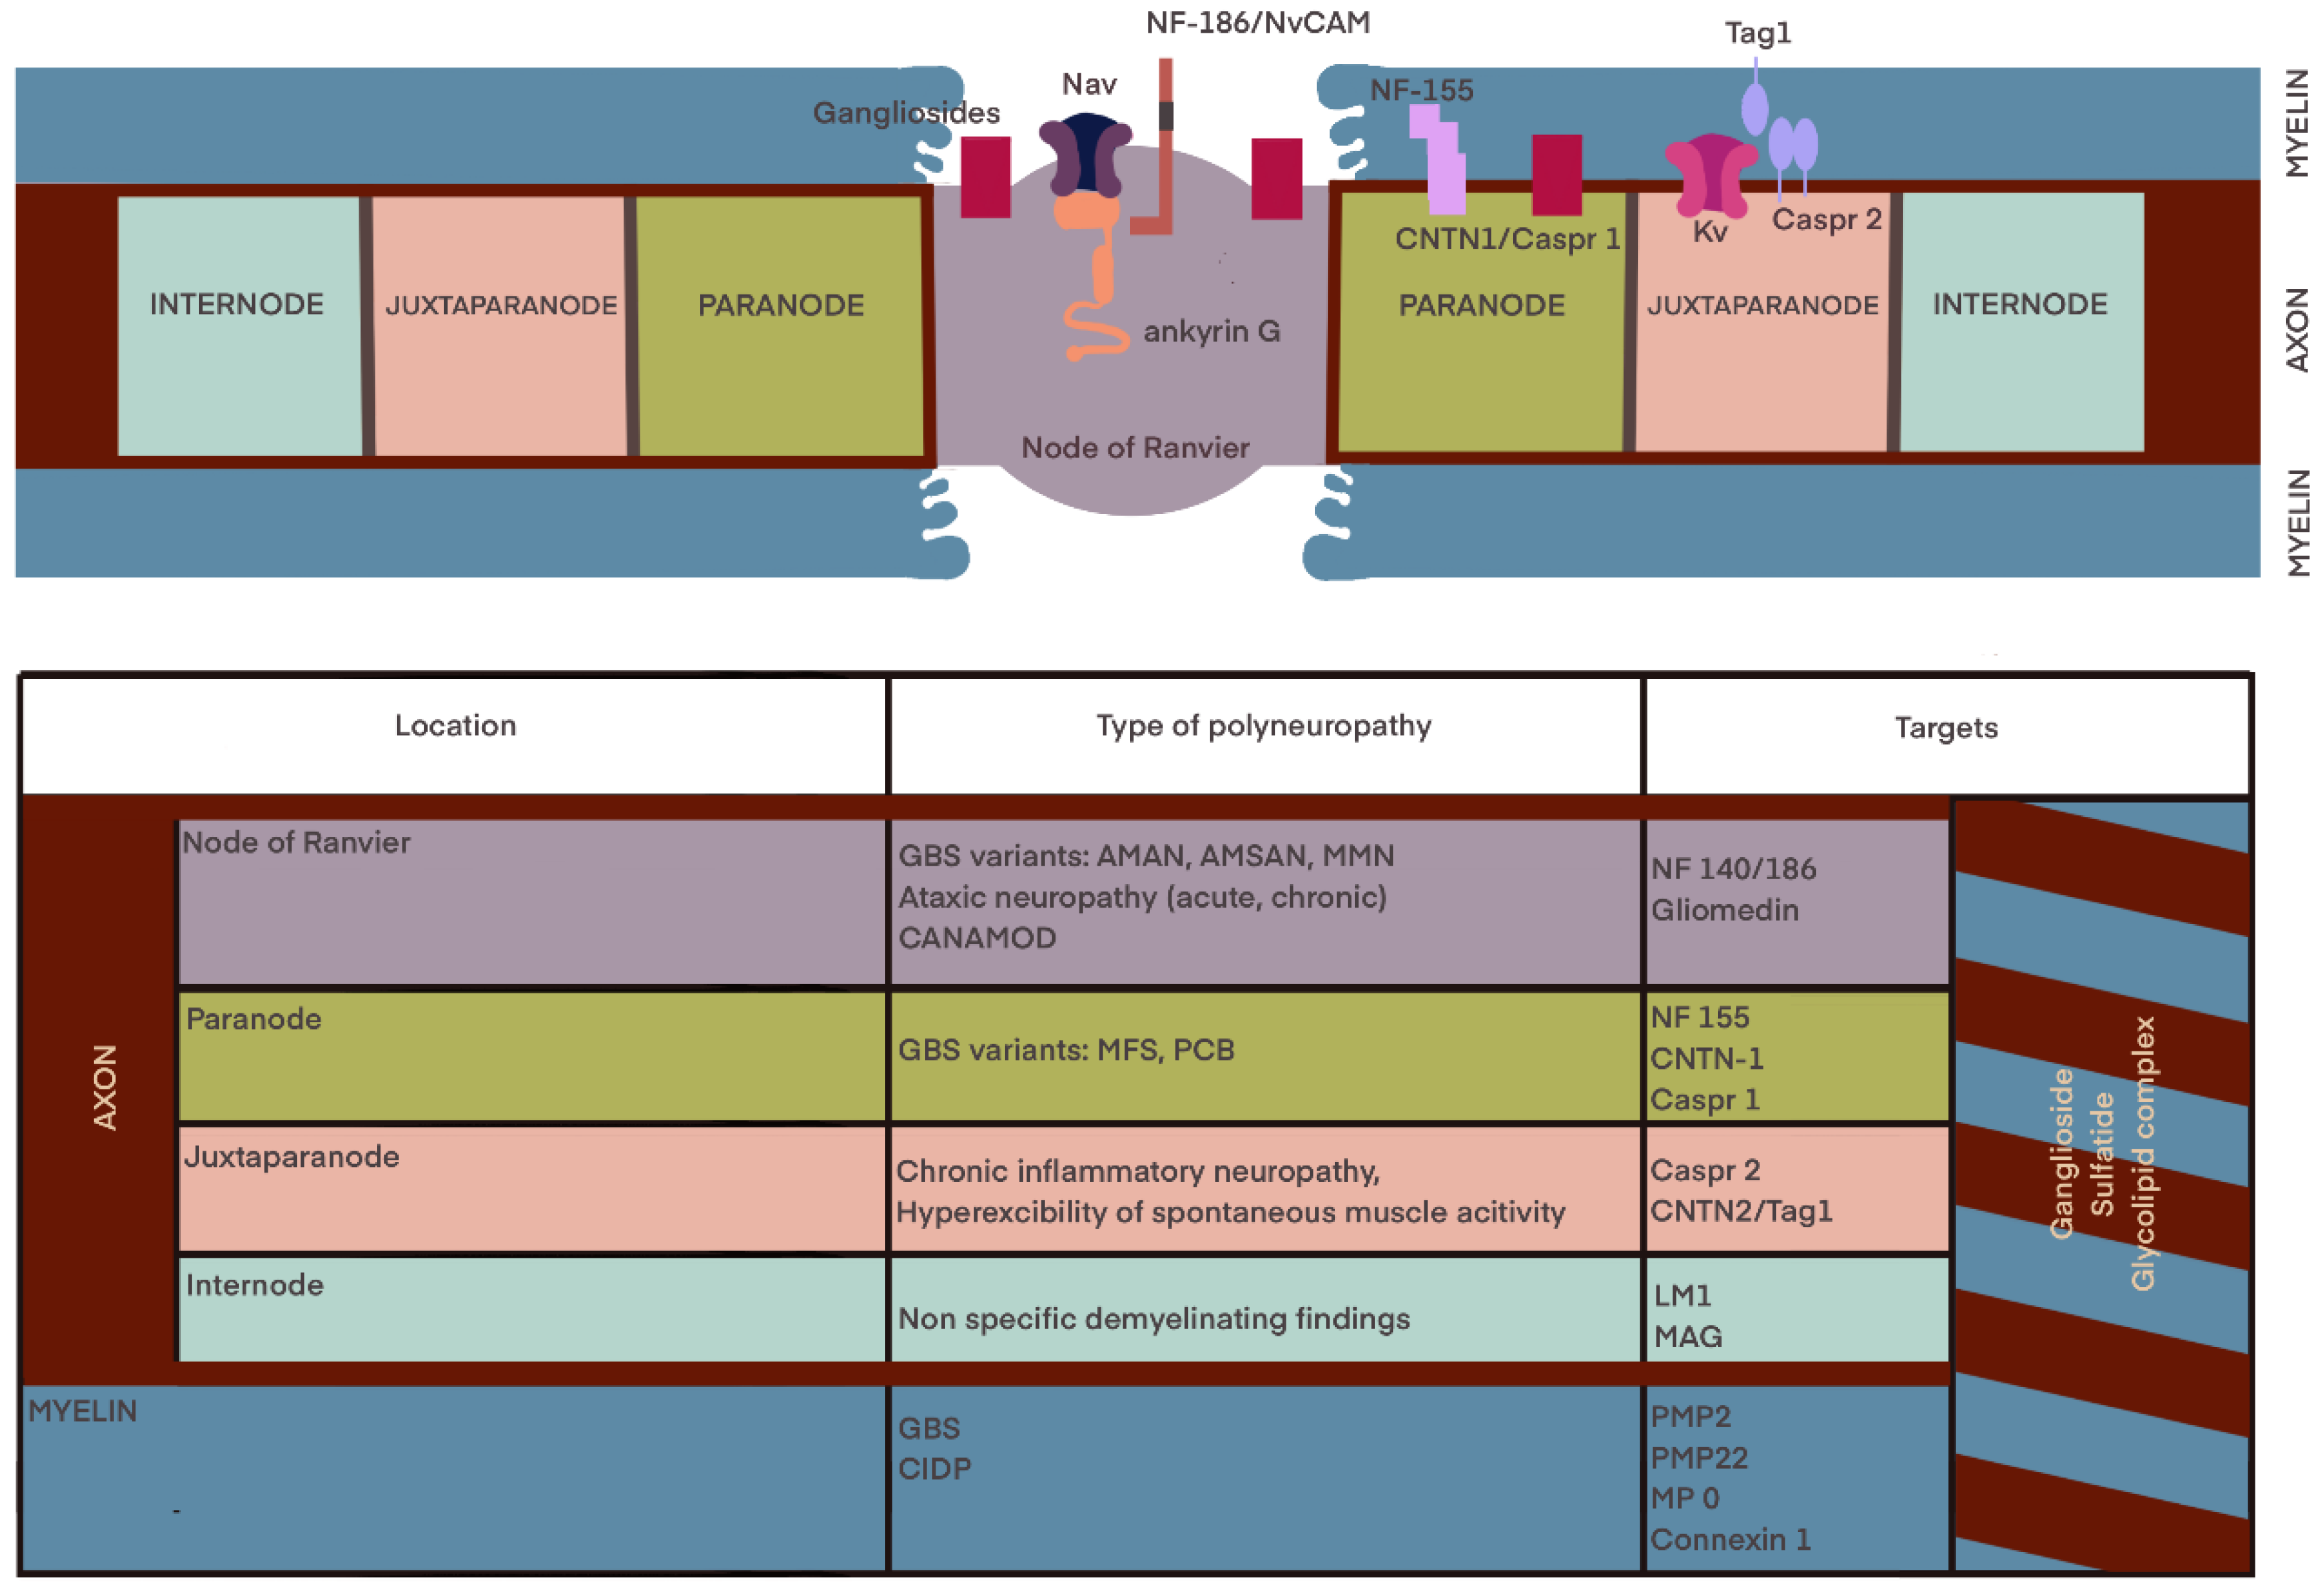

2.1.1. The Molecular Diagnostic

3. The Electrodiagnosis